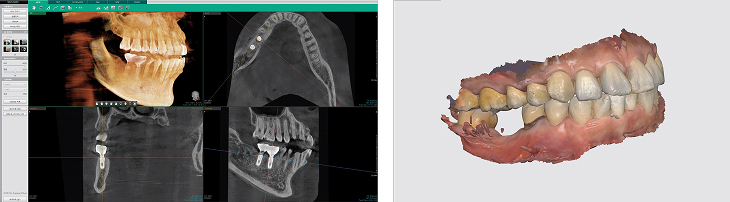

임플란트 시술 전 구강 스캐너로 채득한 구강스캔 데이터와 3D CT 영상을 이용해

치아, 잇몸, 신경, 혈관의 위치를 3차원으로 정밀하게 분석하여 안전한 식립 위치를 미리 파악합니다.

컴퓨터 디지털 시뮬레이션으로 임플란트 수술시 최적의 식립 위치, 각도, 깊이를 사전에 계획합니다.

임플란트 시술 전 구강스캔데이터와 3차원 CT영상을 이용해 입 안의 입체적 환경을 재현해 치아와 잇몸뼈, 신경의 위치까지 분석하여

임플란트가 들어갈 최적의 위치를 찾아 임플란트 치근을 정확하게 심습니다.

수술 전 미리 컴퓨터로 3D 분석 후 임플란트 시술에 들어가기 때문에 시술시간이 짧고, 수술 성공률이 높습니다.

• STEP 01 3D-CT 정밀진단

3차원 데이터를 바탕으로 환자분의 뼈, 잇몸, 신경 등을 종합적으로 고려하여 정밀진단을 실시합니다.

• STEP 02 컴퓨터 가상수술

정밀진단 데이터를 바탕으로 가상시뮬레이션을 통해 최적의 임플란트 식립위치, 각도, 깊이 등을 계획합니다.